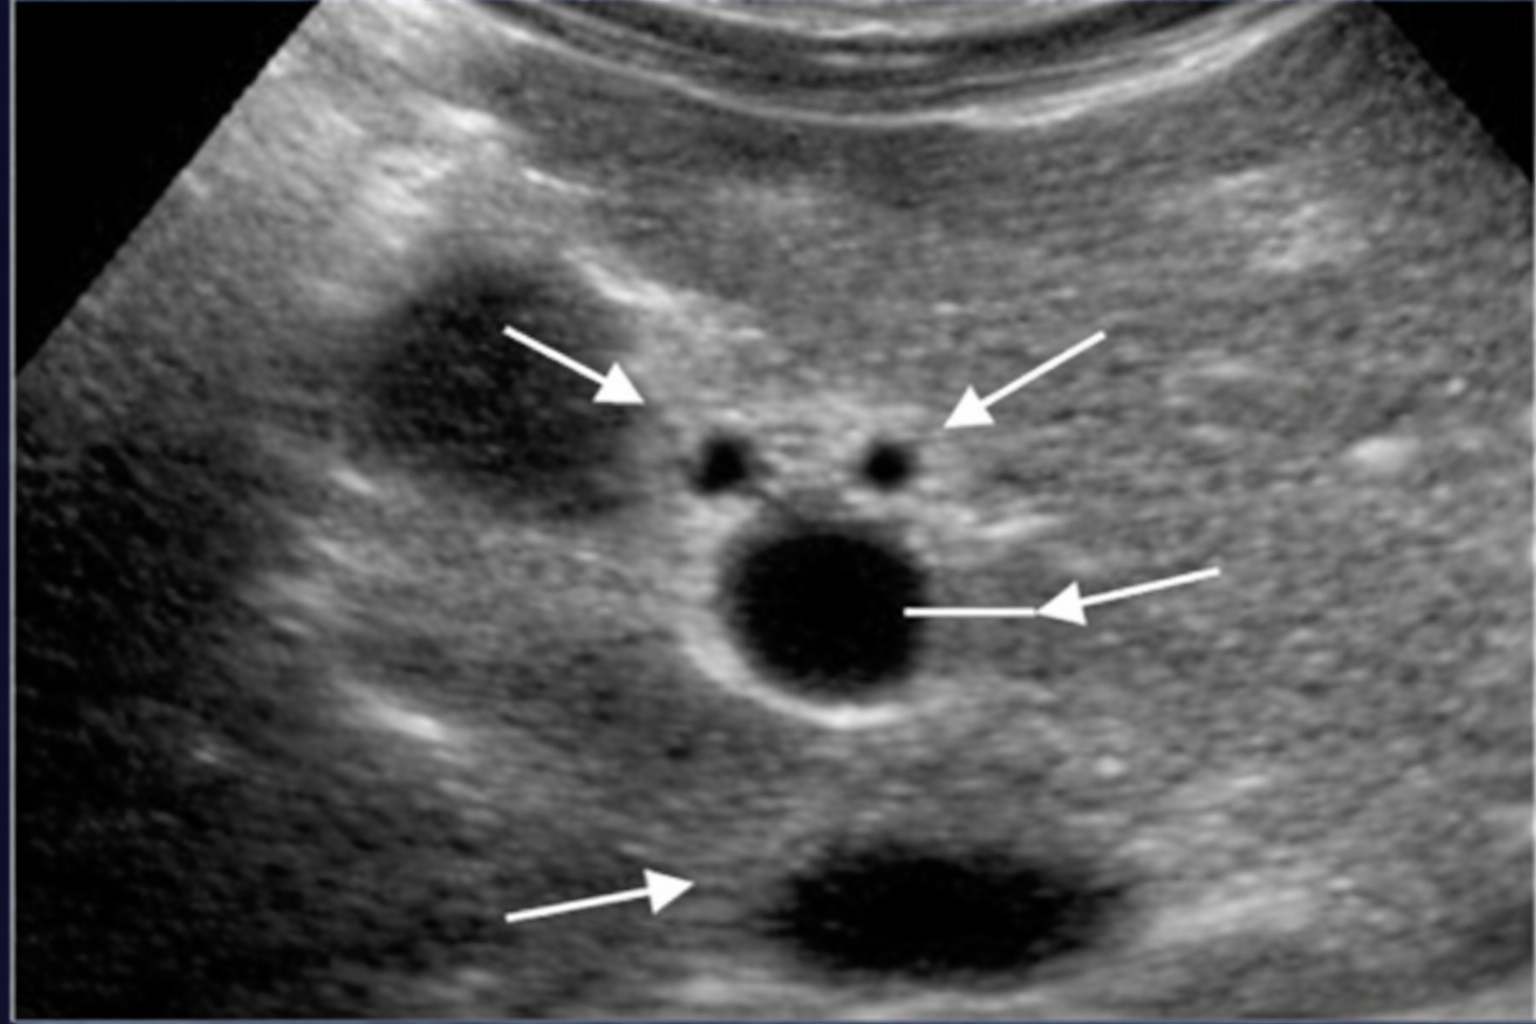

Label Anatomy of PortaHepatis TRV